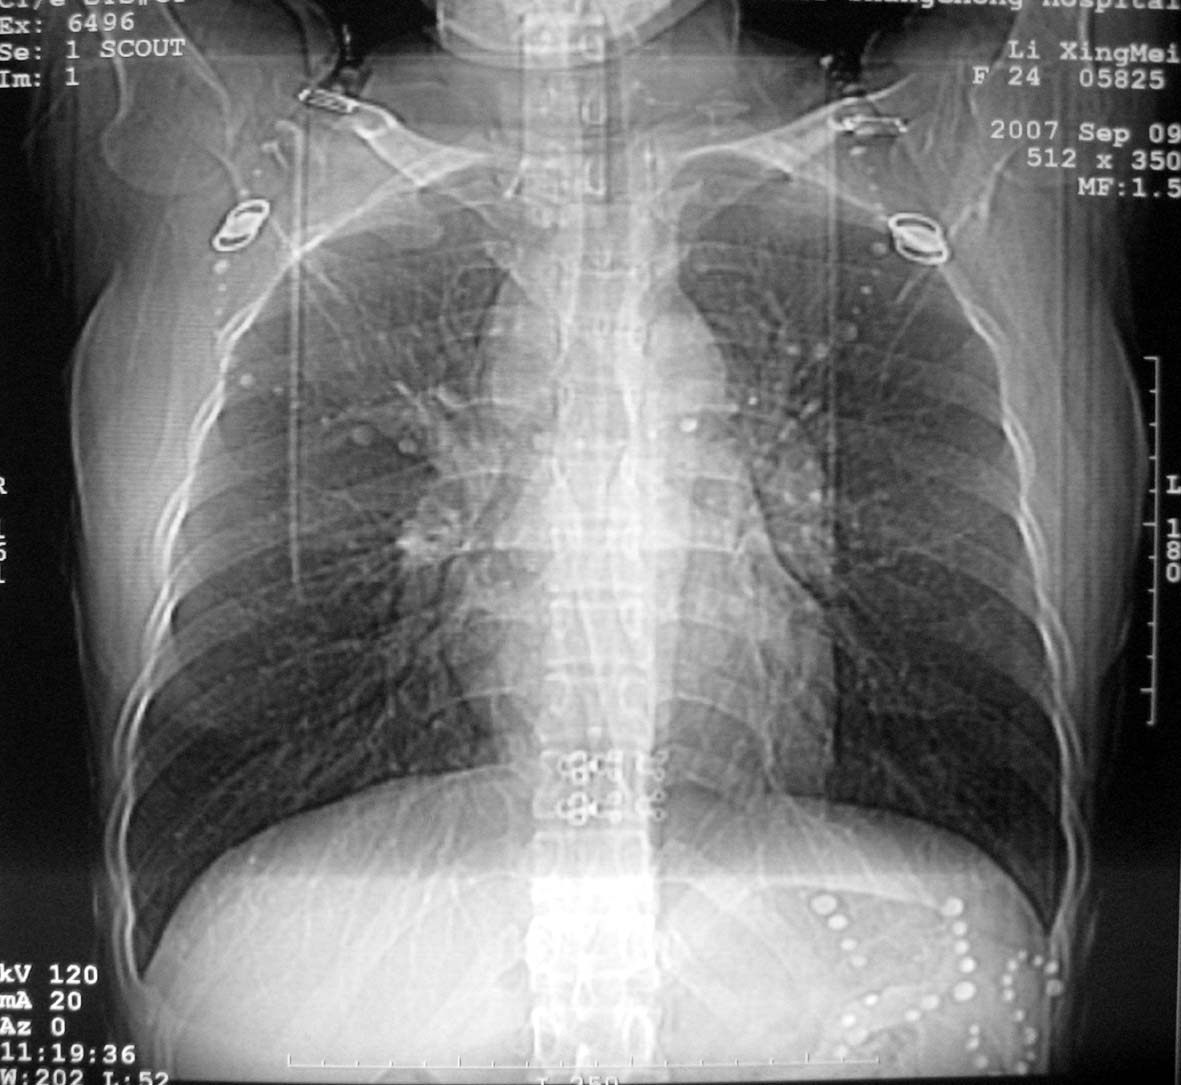

以下是引用qiuleiyu在2007-9-14 19:12:00的发言:[br]纵隔(气管旁组\\隆突下\\主动脉旁组\\血管前组)及肺门淋巴肿大,边界欠清.密度均匀,内无明确钙化.[br]结合临床症状考虑;结节病可能大.[br]鉴别;1,淋巴瘤,可有全身浅表淋巴肿大,肝脾大,发热等.肿大淋巴主要为气管旁组及血管前组及主动脉旁组,肺门肿大不明显.典型者为冰冻纵隔.[br] 2,转移瘤;多见于肺癌,按淋巴链分布肿大,单侧肿大多见,常可见坏死.[br] 3,castlemans;增强后明显血管样强化.内部可有分支状钙化,蜘蛛状瘢痕.周边可有粗大血管.[br] 4,结核;67%有肺部结核灶,肿大淋巴结节,内部可有钙化,增强环状或分格样强化.